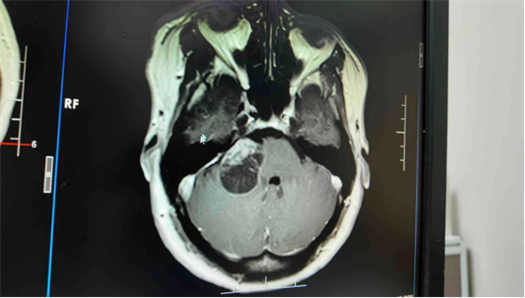

该院神经外科资深专家鲁明主任医师接诊后,发现患者右侧桥小脑角占位压迫听神经,粗测右耳听力明显下降,初步考虑是听神经鞘瘤。

随后,鲁明带领神经外五科为患者行右侧桥小脑角占位切除术。术中,医生在保留听神经和面神经功能的前提下全切肿瘤。

术后病理结果证实是听神经鞘瘤,而群姐的右耳听力恢复清晰,外界声音大一点也不会再嗡嗡响,走路的平衡性也恢复正常。

“听神经鞘瘤是起源于内听道前庭神经鞘膜施旺细胞的良性肿瘤。”鲁明进一步解释,该肿瘤位于内听道及桥小脑角区域,随着体积增大,会逐渐压迫周围的蜗神经、面神经甚至脑干,进而引发听力下降、耳鸣、眩晕等症状,严重时可能危及生命。